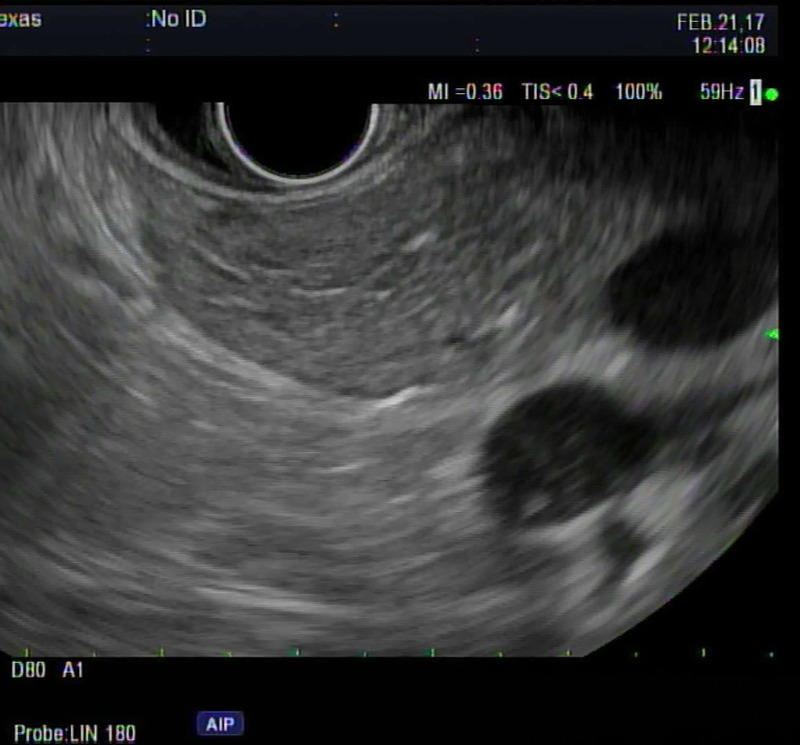

背景和目的:脂肪性胰腺(FP),传统上被认为是一种良性发现,最近由于越来越多的证据将其与各种疾病状态联系起来,包括胰腺癌(PC)的风险增加,因此一直受到密切关注。方法:回顾性研究2007年8月至2023年10月在单一机构接受EUS的患者,由一名具有25年以上经验的超声医师进行。针对在EUS期间确诊为FP的个体,我们将这些发现与EUS前后3个月或1年内进行的计算机断层扫描/磁共振成像(CT/MRI)的相应发现进行了比较。结果:纳入91例患者,并在EUS检查中确定为FP。高危患者中最常见的适应症是PC筛查(35.16%)。进行EUS检查时,65.93%的患者体重指数(BMI)≥30,63.73%的患者患有高血压,32.96%的患者患有2型糖尿病。在91例患者中,70例在EUS检查后3个月内进行了CT或MRI检查,仅有15例(21.43%)在影像学上报告了FP。91例患者1年内均行CT或MRI检查,影像学报告FP仅16例(17.58%)。结论:尽管EUS发现FP,但只有21.43%的患者在3个月内在CT/MRI上发现FP,这表明CT/MRI在识别FP方面的准确性低于EUS,或者在现实环境中可能漏报FP,即使在三级医疗中心也是如此。考虑到FP作为几种重要疾病和促进胰腺癌发生途径的潜在前体的作用,这种报道的差异值得注意。

Background and objectives: Fatty pancreas (FP), traditionally perceived as a benign finding, has been undergoing scrutiny lately due to growing evidence linking it to various disease states, including increased risk for pancreatic cancer (PC).

Methods: A retrospective study of patients who underwent EUS at a single institution from August 2007 to October 2023, conducted by one endosonographer with more than 25 years of experience. Focusing on individuals identified with FP during EUS, we compared these findings with corresponding findings on computed tomography/magnetic resonance imaging (CT/MRI) conducted within 3 months or 1 year prior to or following EUS.

Results: Ninety-one patients were included and identified as having FP on their EUS exams. The most common indication for EUS was PC screening in high-risk patients (35.16%). At the time of conducting EUS, 65.93% of patients had a body mass index (BMI) ≥30, 63.73% had hypertension, and 32.96% had type 2 diabetes mellitus (DM). Of the 91 patients, 70 had CT or MRI done within 3 months of the EUS date, and only 15 (21.43%) had FP reported on imaging. All 91 patients had CT or MRI within 1 year, and only 16 (17.58%) had FP reported on imaging.

Conclusion: Only 21.43% of patients had FP on their CT/MRI within 3 months despite EUS findings, suggesting either lower accuracy of CT/MRI compared to EUS in identifying FP or potential underreporting in a real-world setting, even in a tertiary care center. This discrepancy in reporting is noteworthy considering FP's role as a potential precursor to several important conditions and promoting pancreatic carcinogenesis pathways.